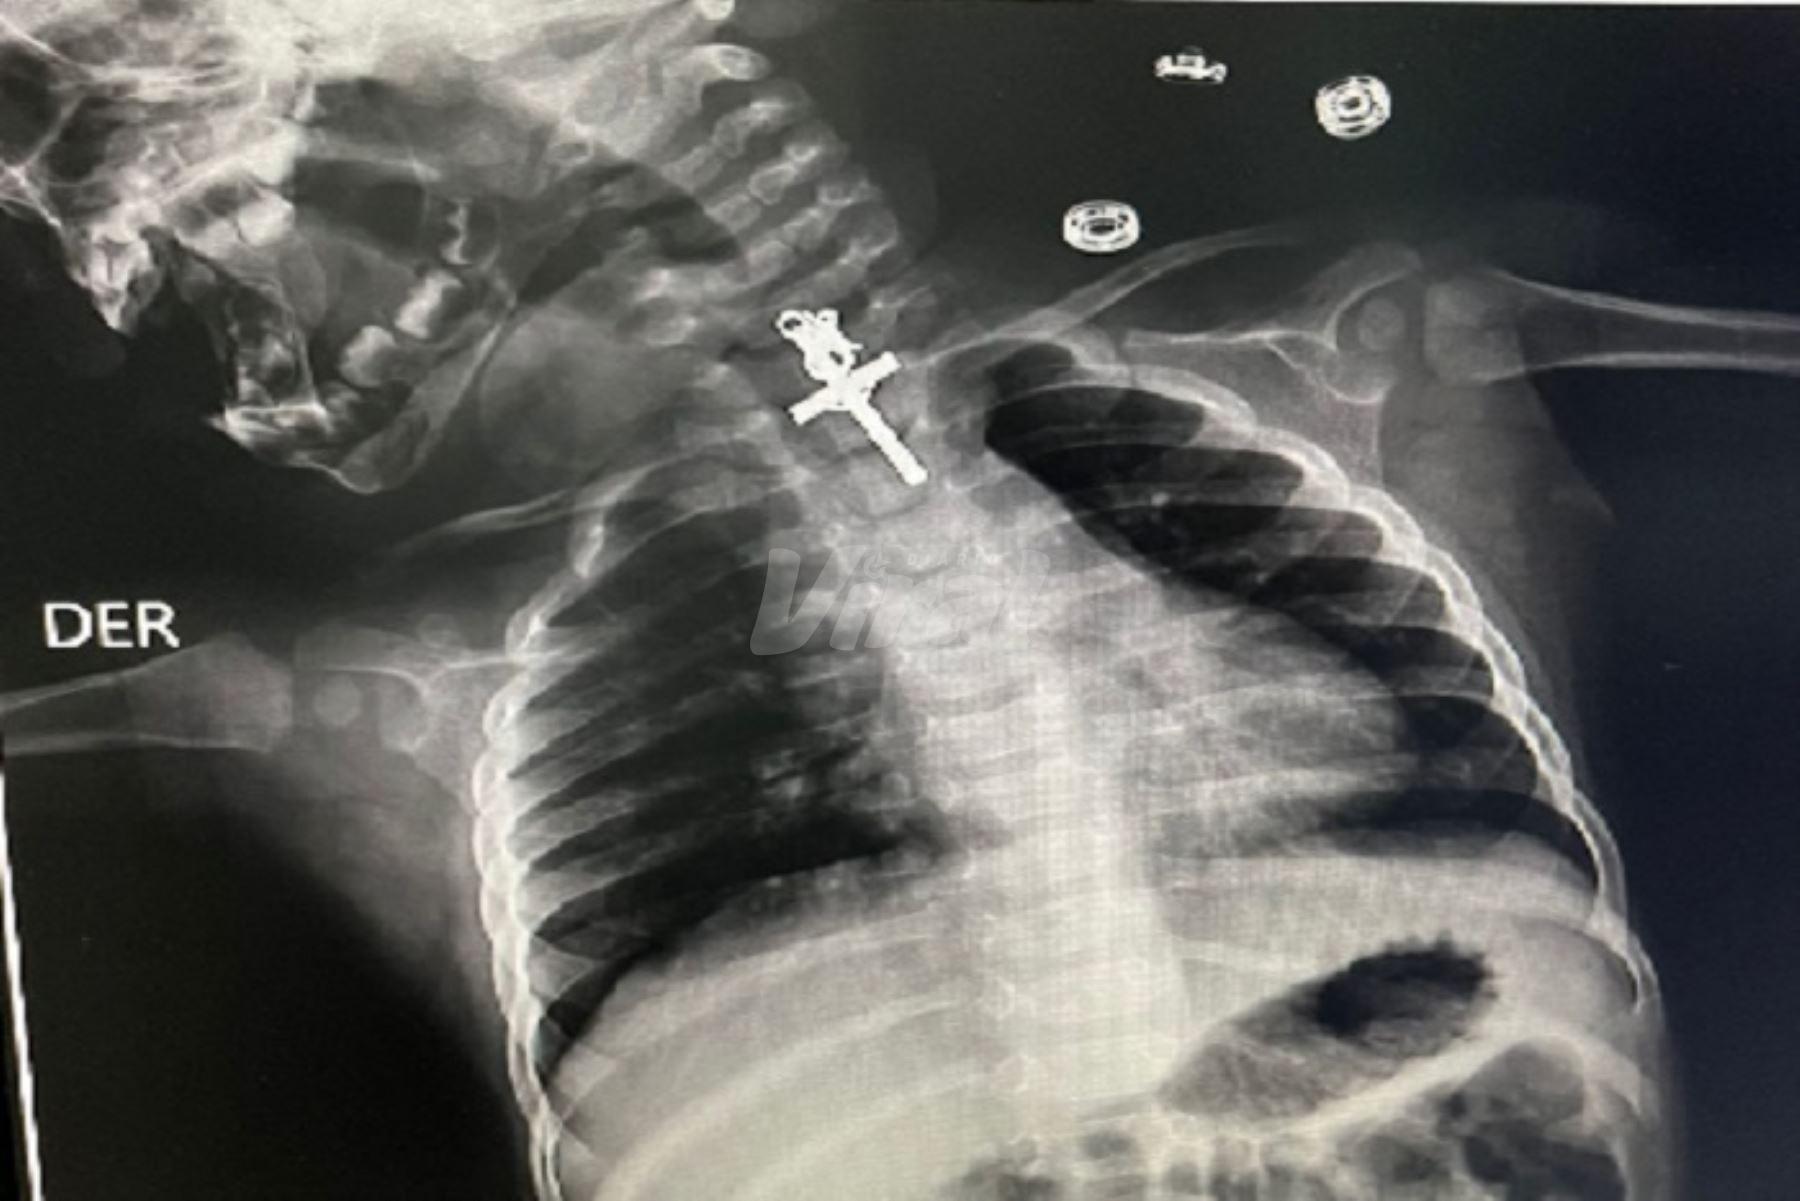

Médicos de hospital de La Libertad salvan vida de bebé tras hallar crucifijo en su esófago